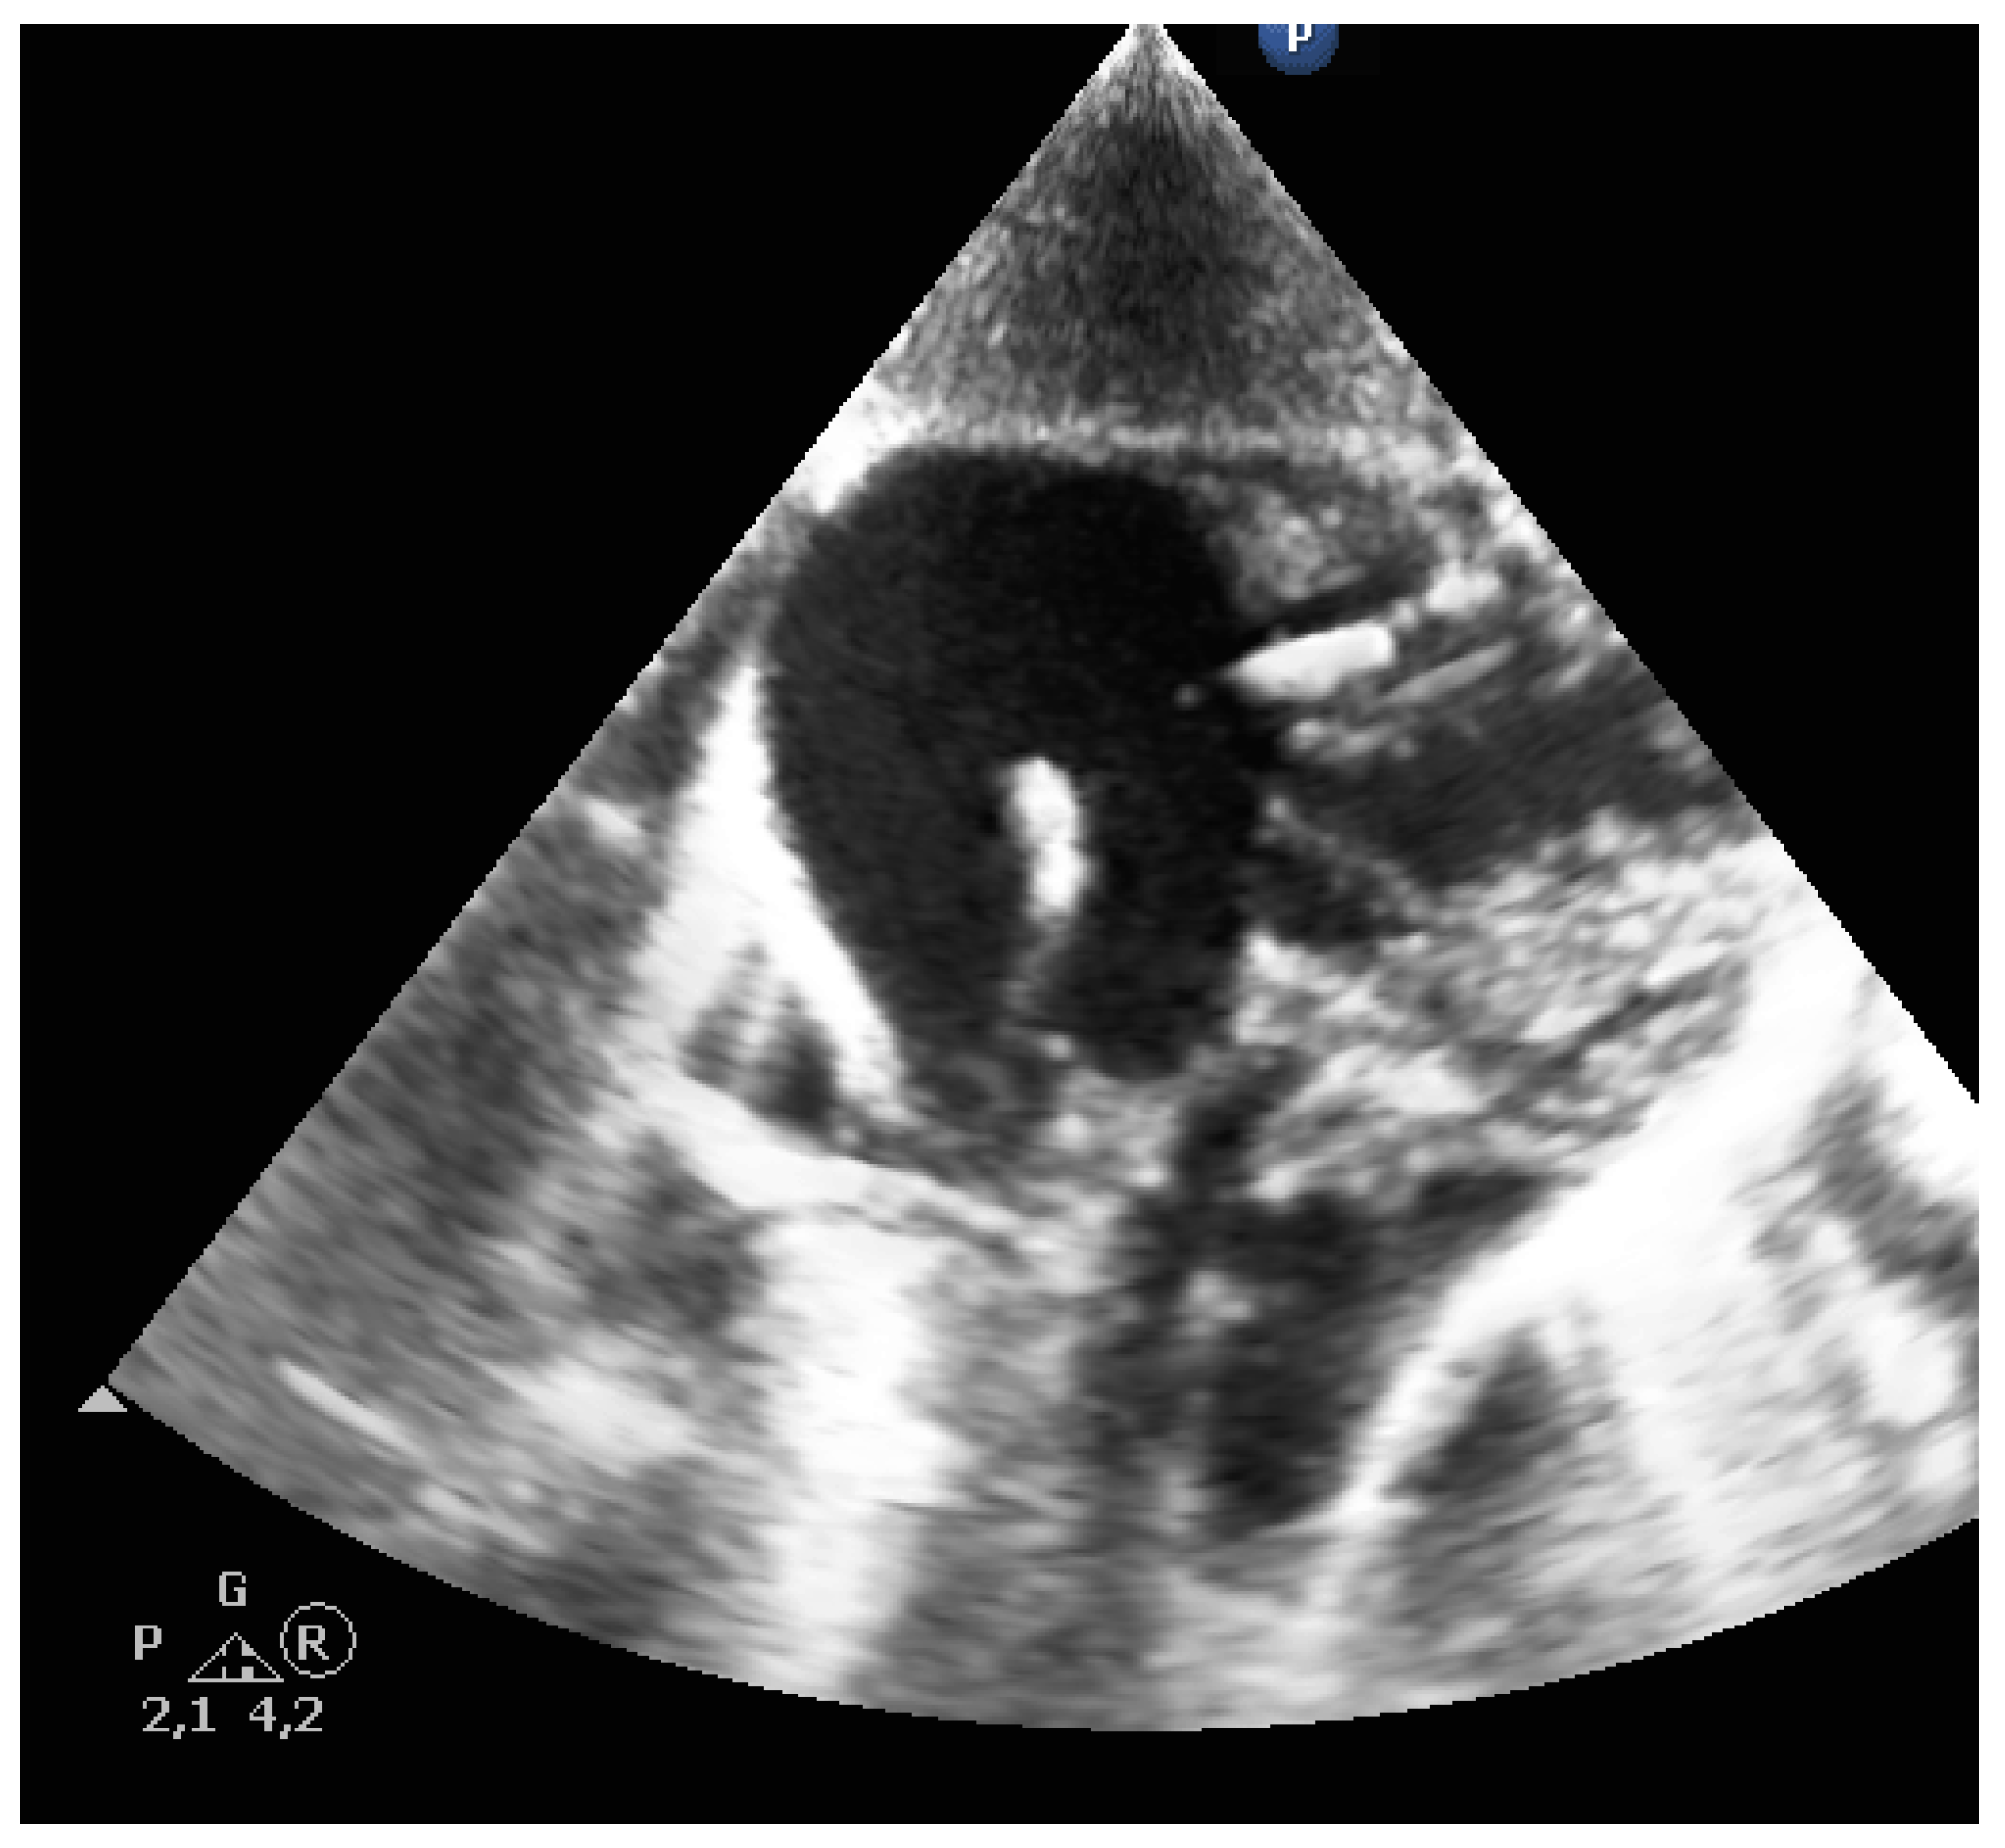

• Second view: parasternal transversal view

A linear transducer, or hockey stick, was used. From the previous position, the probe was rotated 90 degrees. The SVC was visualized in the cross-section, with the brachiocephalic trunk (BCT) and the right carotid artery. The right pulmonary artery (RPA) can be seen longitudinally (Figure 3).

Figure 3. Parasternal transversal view: superior venae cava (SVC), brachiocephalic trunk (BCT), right pulmonary artery (RPA), pericardial effusion (PE).